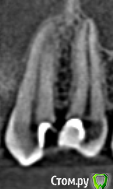

redgoldindigo Опубликовано 18 октября, 2019 Поделиться Опубликовано 18 октября, 2019 Здравствуйте. Меня замучила зубная боль, к своему стоматологу доверия нет, поэтому решила сделать КТ. Если кто может помочь в его расшифровке, буду благодарна. Может быть по скриншотам подскажете, это глубокий кариес или что-то еще? Ссылка на комментарий

krokomot Опубликовано 18 октября, 2019 Поделиться Опубликовано 18 октября, 2019 Большая вероятность что пульпа указанных зубов с пломбами инфицирована, требуется лечение. 1 Ссылка на комментарий